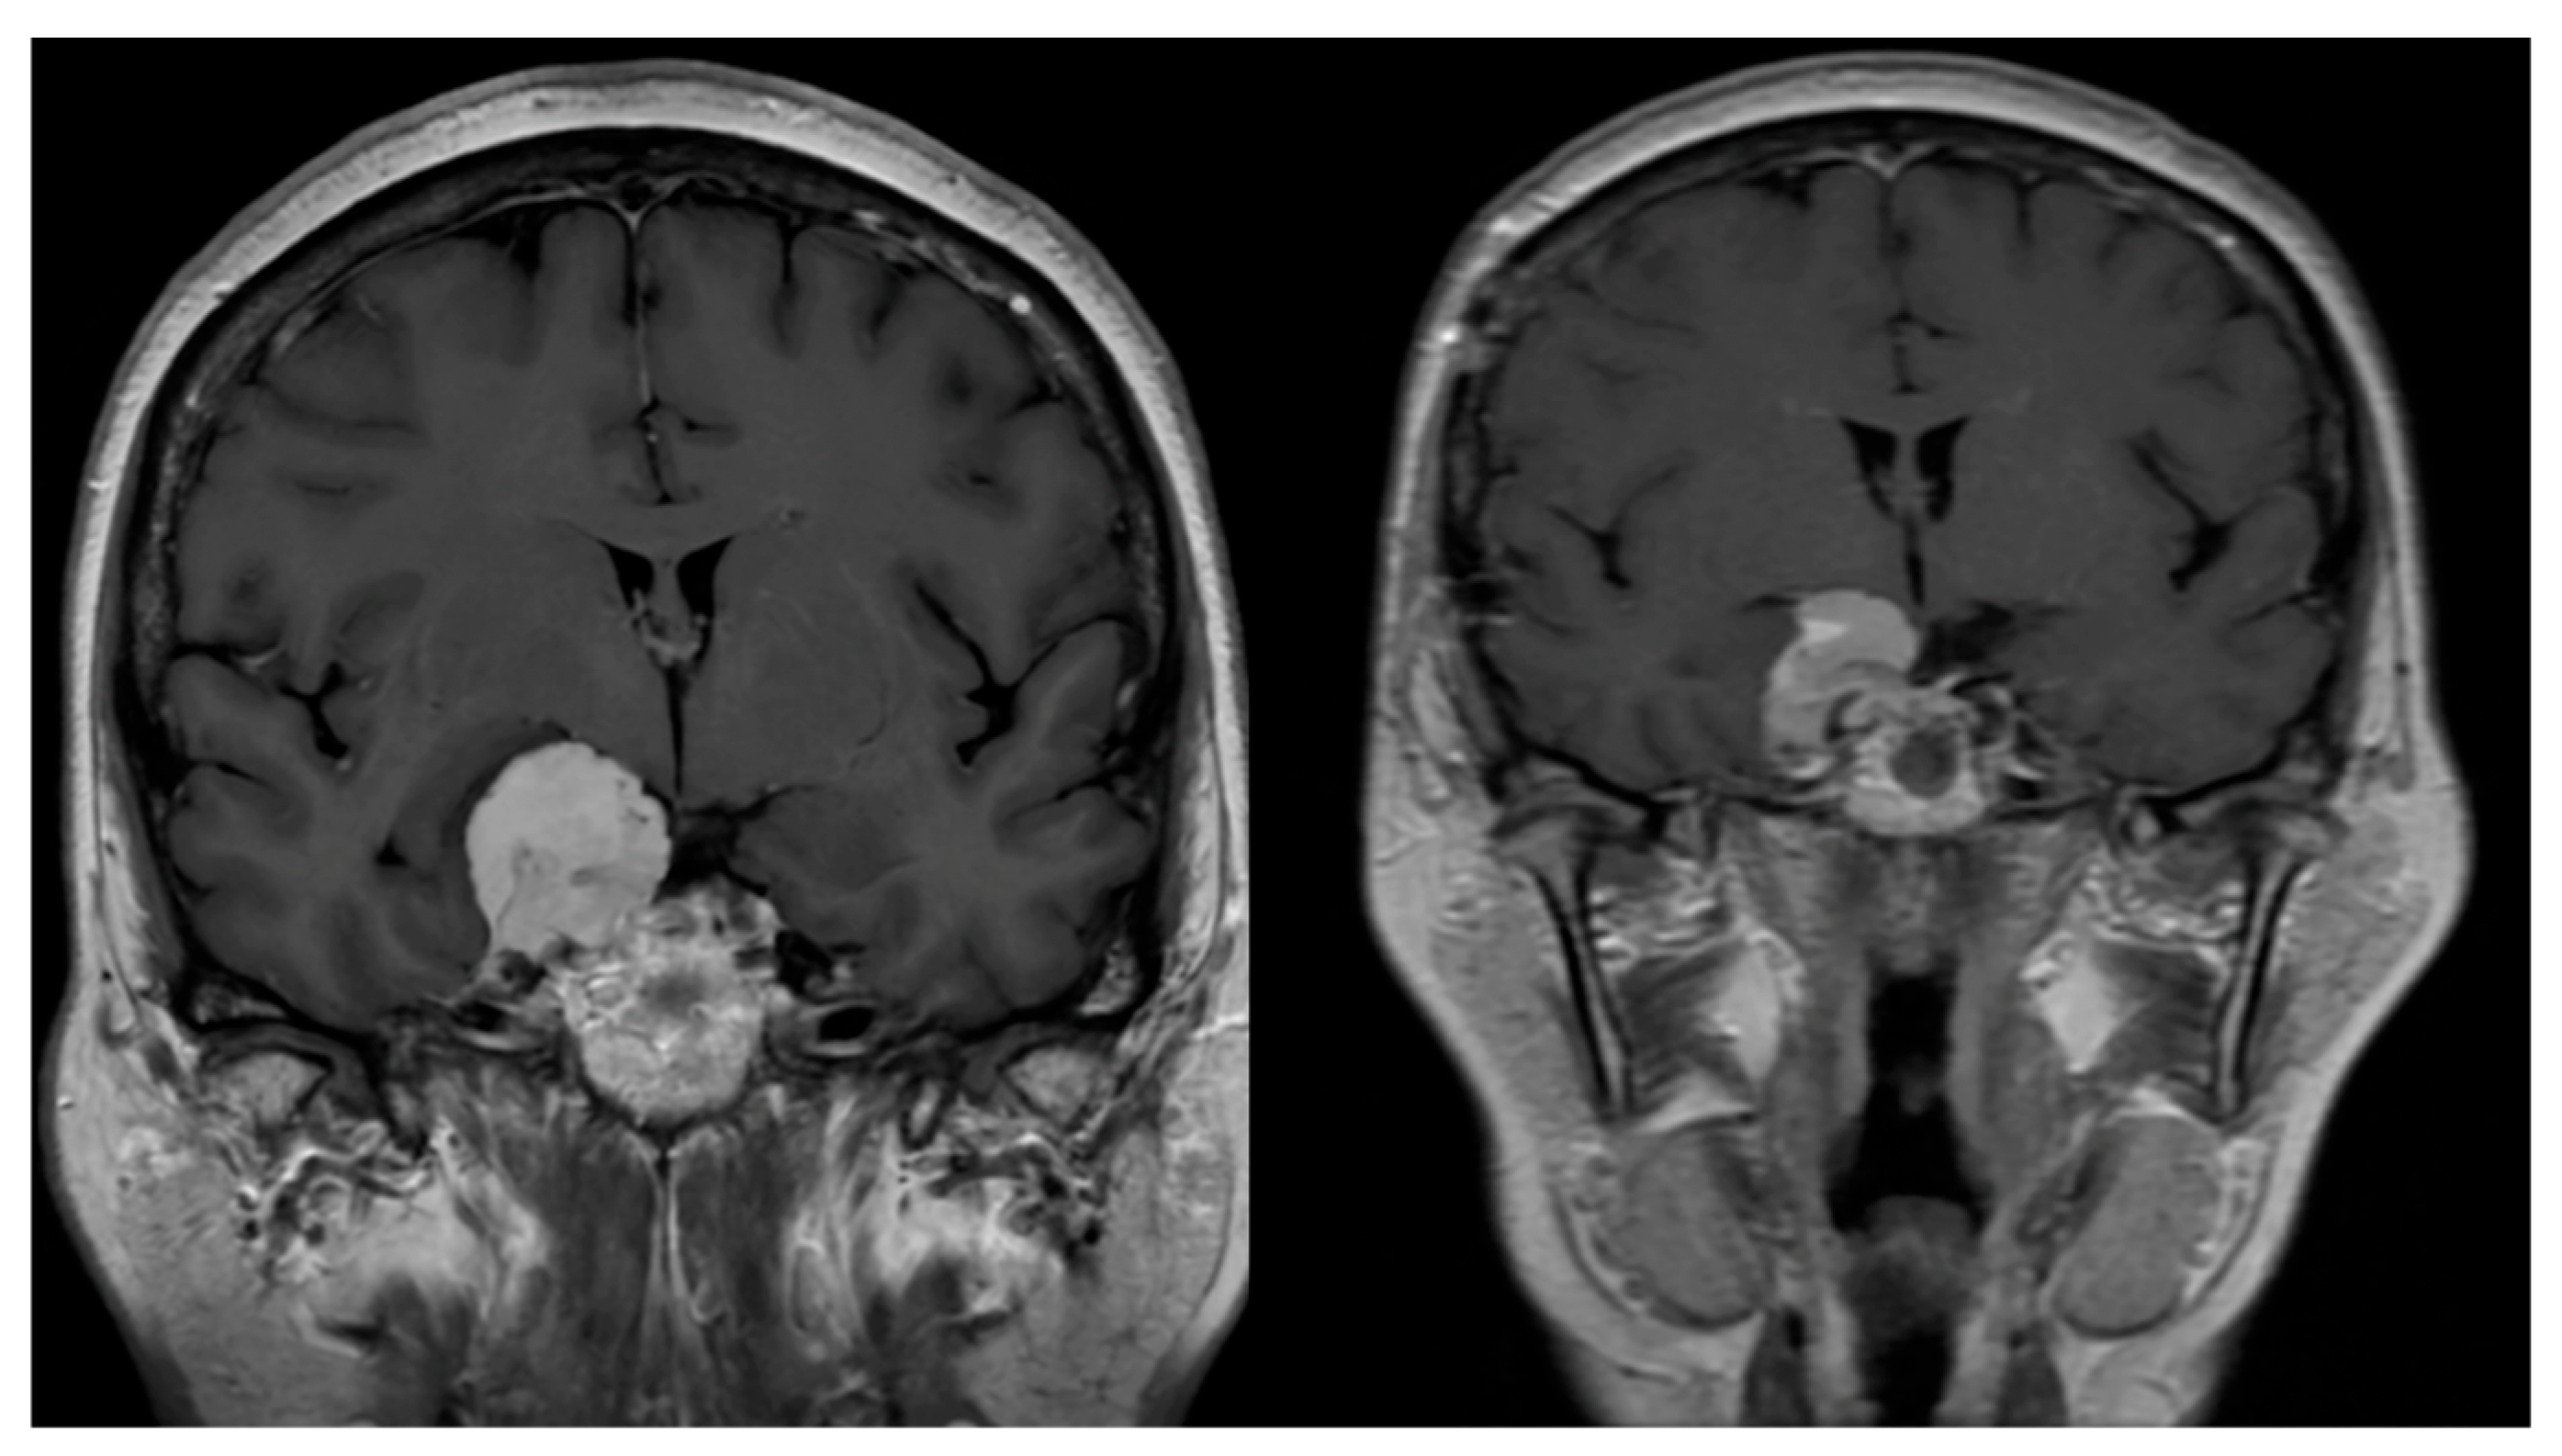

5.3. Complementary Studies

5.3.2. Diffusion Tensor Imaging (DTI) Tractography

- The paroxysmal episodes of divine conviction were directly related to epileptic activity and alteration of the uncinate fasciculus.

- The correlation with alteration of the right uncinate fasciculus supports the hypothesis that this white matter tract may act as a key modulator in the propagation of epileptic activity toward frontal regions involved in meaning attribution.